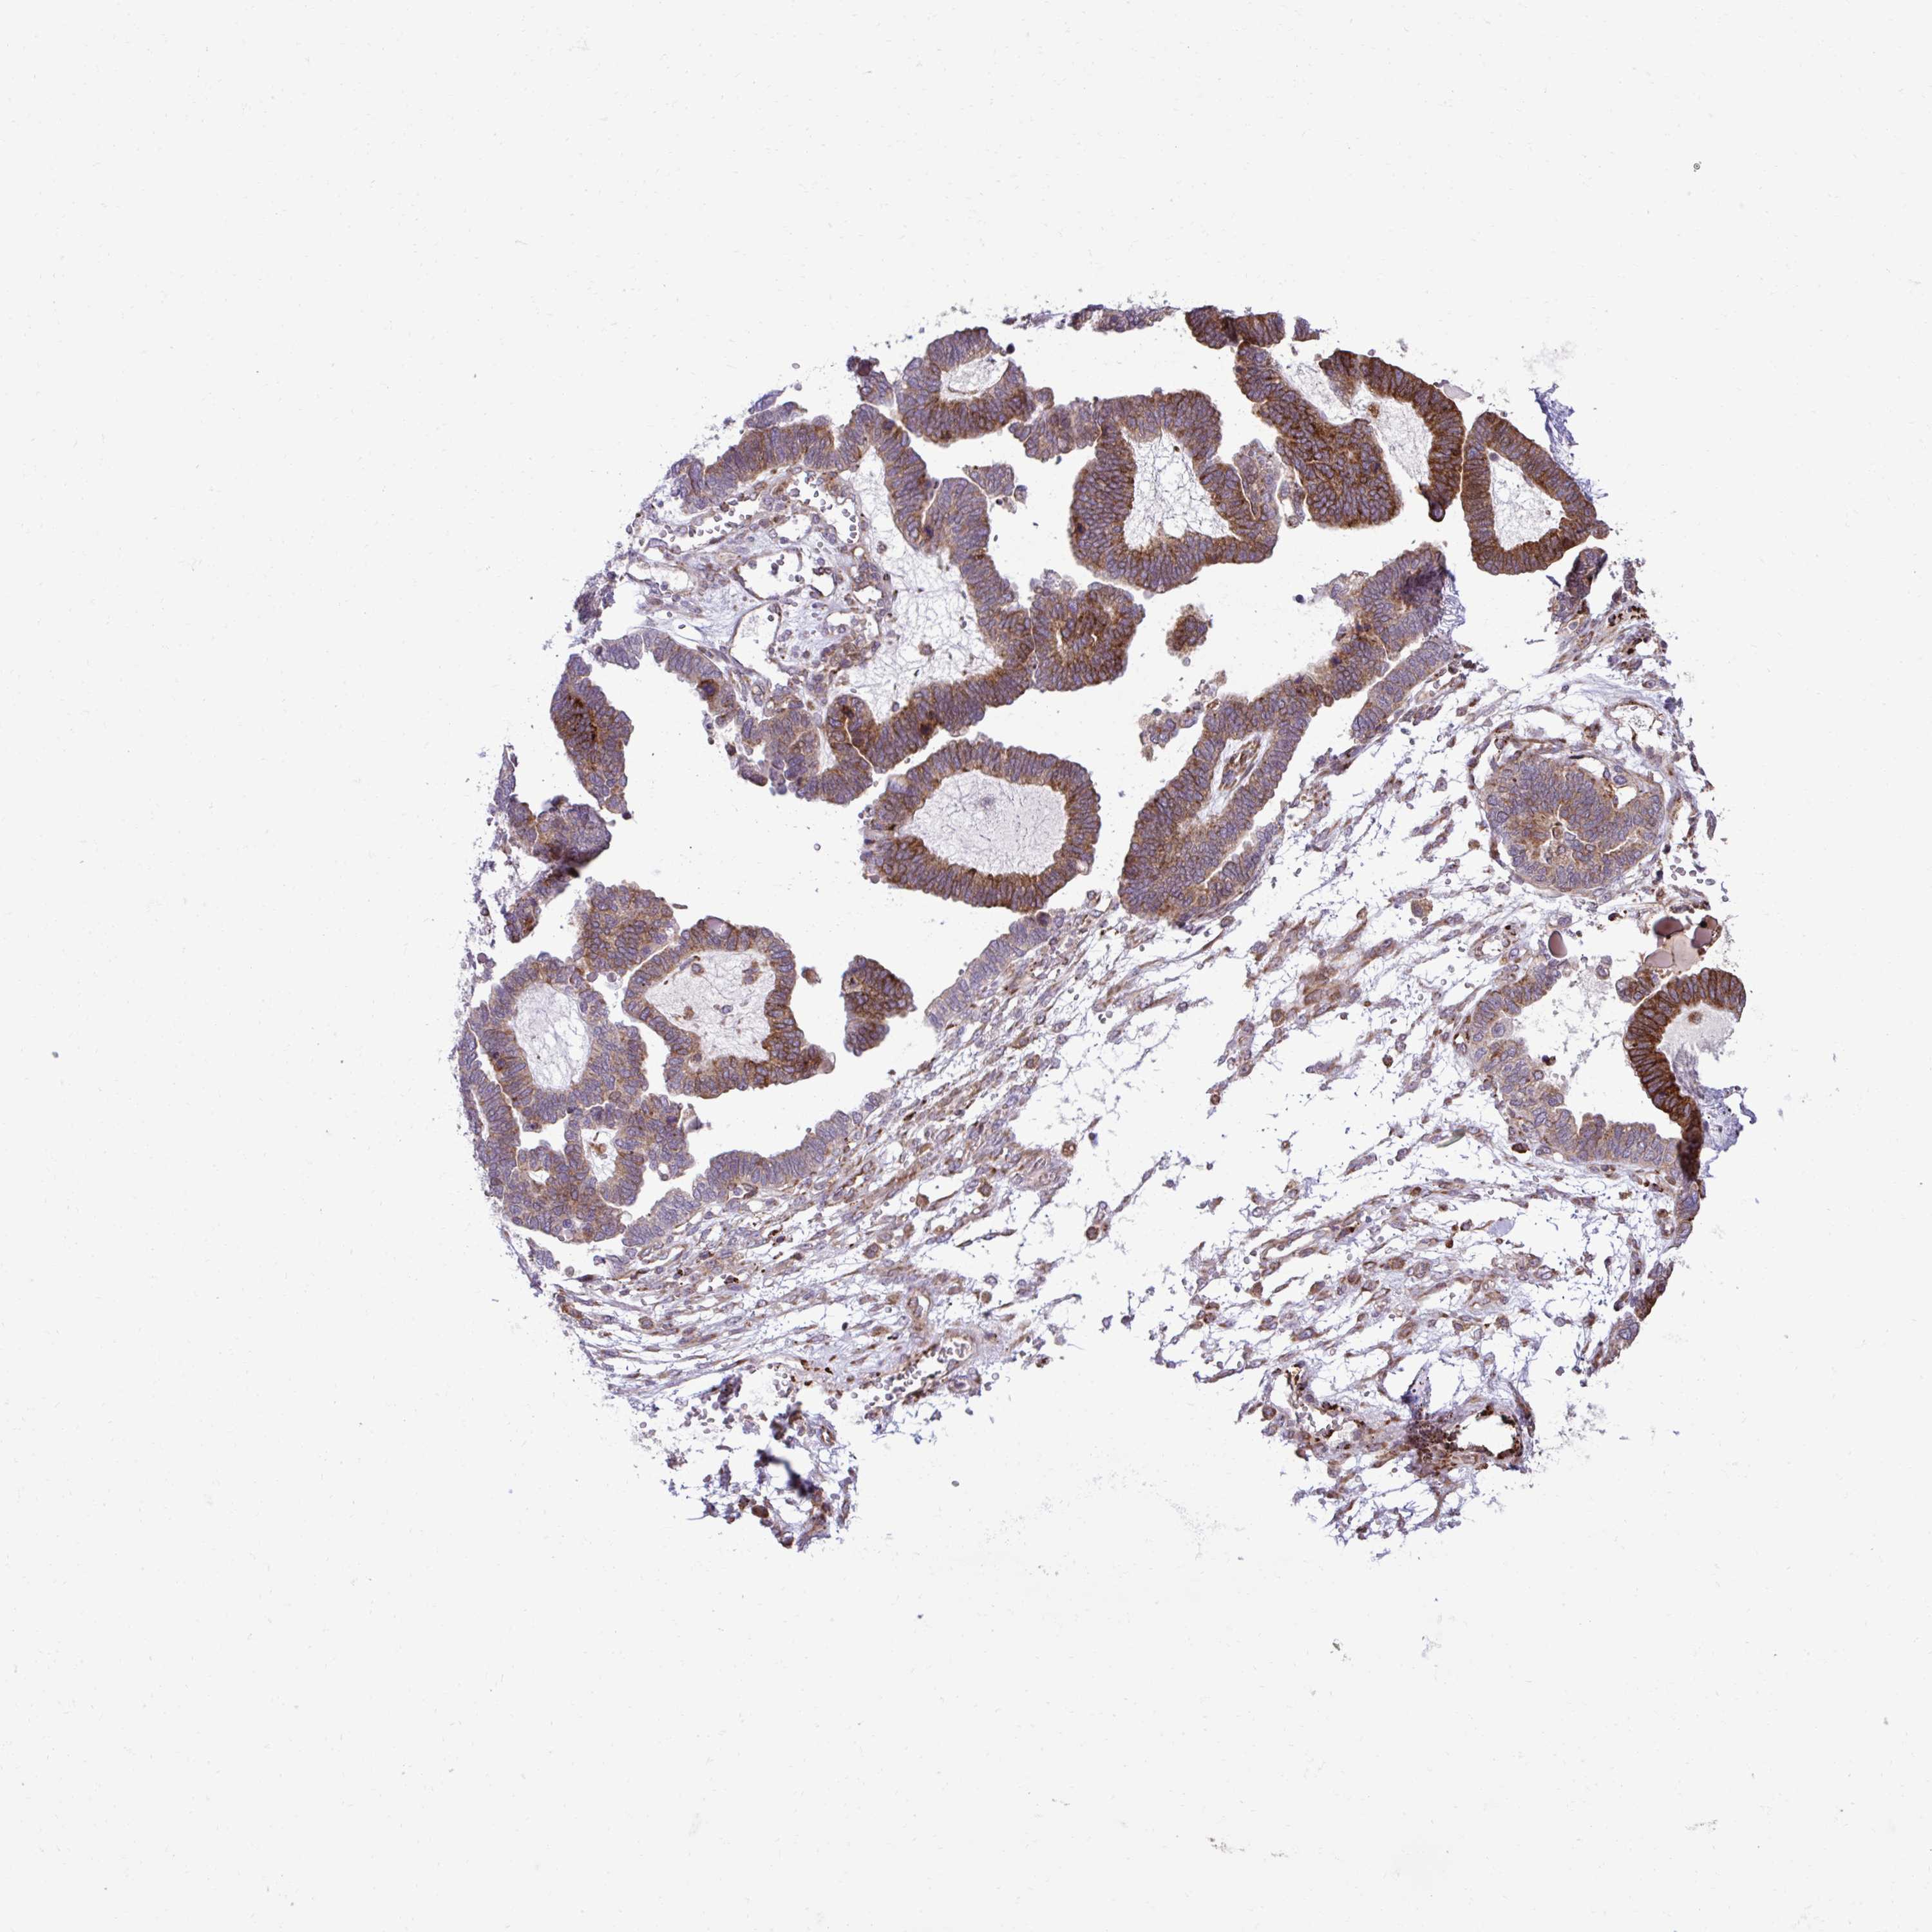

OVARIAN CANCER - Protein expressioni

A mouse-over function shows sample information and annotation data. Click on an image to view it in a full screen mode. Samples can be filtered based on level of antibody staining by selecting one or several of the following categories: high, medium, low and not detected. The assay and annotation is described here.

Note that samples used for immunohistochemistry by the Human Protein Atlas do not correspond to samples in the TCGA dataset.

Antibody stainingi

Antibody staining in the annotated cell types in the current human tissue is reported as not detected, low, medium, or high, based on conventional immunohistochemistry profiling in selected tissues. This score is based on the combination of the staining intensity and fraction of stained cells.

Each image is clickable and will lead to virtual microscopy that enables deeper exploration of all samples and also displays staining intensity scores, fraction scores and subcellular localization as well as patient and tissue information for each sample.

Antibody HPA058455

Antibody HPA061230

Staining

High

Medium

Low

Not detected

Intensity

Strong

Moderate

Weak

Negative

Quantity

>75%

75%-25%

<25%

None

Location

Nuclear

Cytoplasmic/membranous

Cytoplasmic/membranous,nuclear

Cystadenocarcinoma, serous, NOS

Cystadenocarcinoma, mucinous, NOS

Carcinoma, endometroid